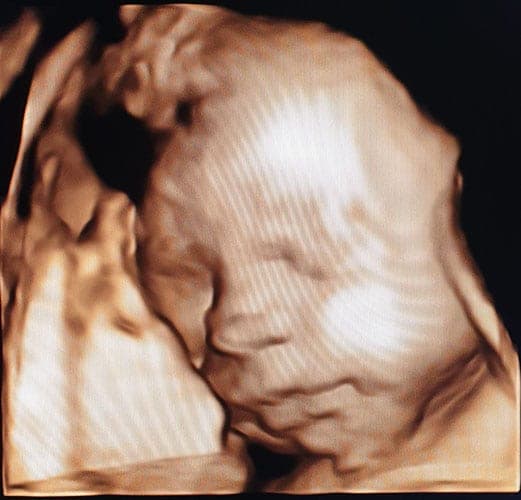

Ultraschallbilder aus dem 3. Trimester (29. bis 40. SSW)

Im dritten Trimester der Schwangerschaft ist das Baby so groß, dass es nicht mehr komplett auf ein Ultraschallbild passt. Nun kann man wunderbare 3D-Ultraschalle des Gesichts machen. In diesem Semester nehmen die Babys nochmal rasant zu und wer Glück hat, kann auf seinem Ultraschall schon erste Gesichtszüge erkennen.

Wer sich jedoch erhofft Gesichtszüge zu erkennen, der wird oft enttäuscht. Zwar kann man beim 3D-Ultraschall schon eine Menge sehen, aber das umgebende Fruchtwasser sorgt in den allermeisten Fällen für starke Störungen.